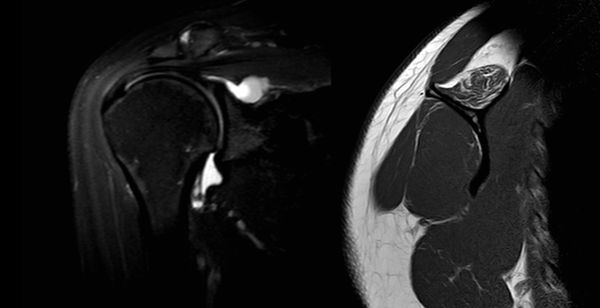

In some cases, Type II SLAP lesions may be associated with the formation of a paralabral cyst. Paralabral cysts associated with Type II SLAP lesions are usually formed in the posterior superior quadrant of the labrum and therefore forms the classical spinoglenoid cyst.

When large, spinoglenoid cysts may encroach upon the suprascapular nerve and result in neuropathy (Figure 3). Unlike suprascapular neuropathy due to compression at the suprascapular notch, suprascapular neuropathy from a spinoglenoid cyst usually results in isolated infraspinatus atrophy and weakness and spares the supraspinatus.

Figure 3. MRI sagittal view of a spinoglenoid cyst lesion with T2 sequences. Note the infraspinatus edema reflecting suprascapular nerve compression. Reproduced from XX with permission.

However, a selective compression of the supraspinatus branch is possible (Figure 4).

Selective compression of supraspinatus branch of suprascapular nerve.

Figure 4. Left: MRA coronal view with T2 sequences revealing a large spinoglenoid cyst. Right: MRI sagittal view of the same patient with T1 sequences of a fatty infiltrated supraspinatus. Reproduced from XX with permission.